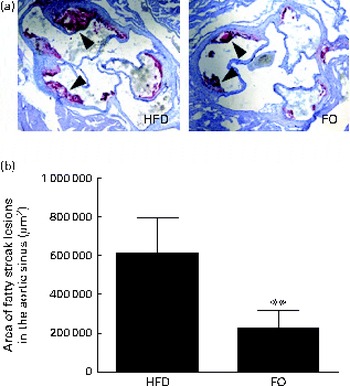

Atherosclerotic plaque area

We then quantified the total atherosclerotic lesion area in HFD- and FO-fed apoE− / − mice. The HFD produced aortic atherosclerotic lesion areas in the aortic sinus, as shown by oil red O staining (Fig. 3(a)). Treatment with FO significantly decreased the mean atherosclerotic lesion area ((2·25 (sd 0·91)) × 105μm2) in the aortic sinus by 62·90 (sd 7·84) % compared with HFD-fed apoE− / − mice ((6·07 (sd 3·35)) × 105μm2) (P< 0·01; Fig. 3(b)). These data clearly showed that chronic FO treatment significantly inhibited the formation of atherosclerotic lesions in HFD-fed apoE− / − mice.

Fig. 3 Atherosclerotic lesions. (a) Representative photomicrographs of the aortic sinus stained with oil red O are shown. The arrows indicate fatty streak lesions. 100 × magnification. (b) The area of fatty streak lesions in the aortic sinus is calculated with software LAS version 3.8. Values are means, with standard deviations represented by vertical bars. ** Mean value was significantly different from that of the high-fat diet (HFD) group (P< 0·01). FO, high-fat diet enriched with 10 % fish oil.